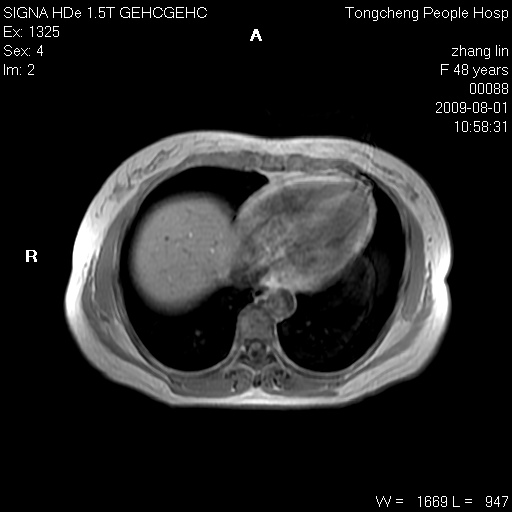

女,48岁。健康体检,彩超发现右肾占位性病变。平素健康。

临床诊断:右肾占位性病变,性质待定(囊肿?肿瘤?)。

上中腹部mr平扫+增强扫描,图像如下:

右肾上极见一类圆形病灶,t1wi呈等信号t2wi呈等高混杂信号,三期增强无强化,边界清---考虑囊肿出血。

肝囊肿

慢性胆囊炎